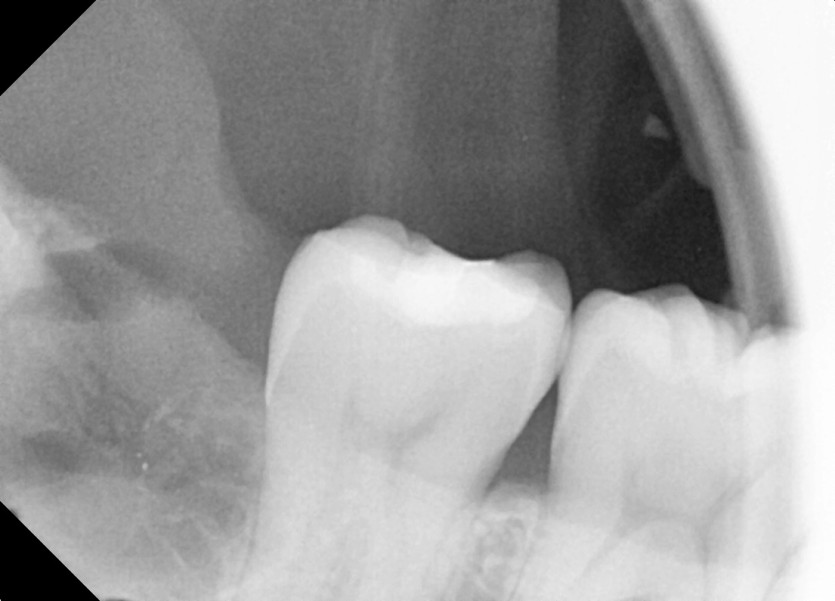

#18,48 사랑니 발치

구강 외과 전문의가 당일 발치했습니다.